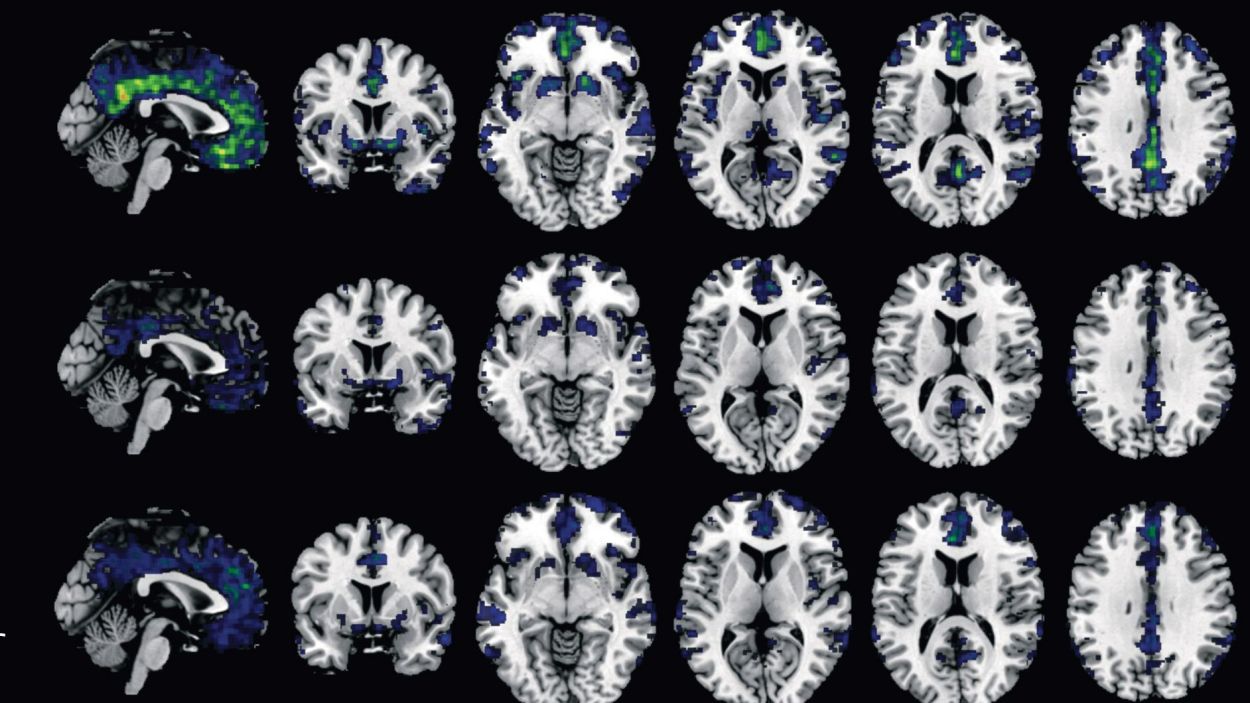

La teoria prevalent sobre les causes de l’Alzheimer indica que estan relacionades amb l’acumulació anòmala de dues proteïnes, beta-amilode i tau. En els teixits neuronals, però encara hi ha moltes incògnites sobre els processos que desencadenen aquesta malaltia neurodegenerativa. Un estudi amb la participació de la Universitat de Girona i la Universitat Pompeu Fabra, aporta […]

L’Institut Hospital del Mar d’Investigacions Mèdiques (IMIM) conjuntament amb el Barcelonaßeta Brain Research Center (BBRC) de la Fundació Pascual Maragall i amb la Universitat de Göteborg han trobat 4 biomarcadors sanguinis útils per al diagnòstic de l’Alzheimer. En van analitzar 9, i 4 podrien servir en el diagnòstic de la malaltia i detectar així a […]